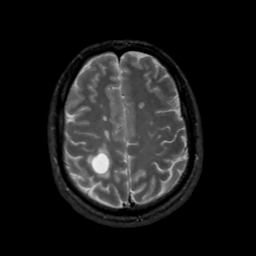

MR Study #7, March 24, 1991 -- Slice #37